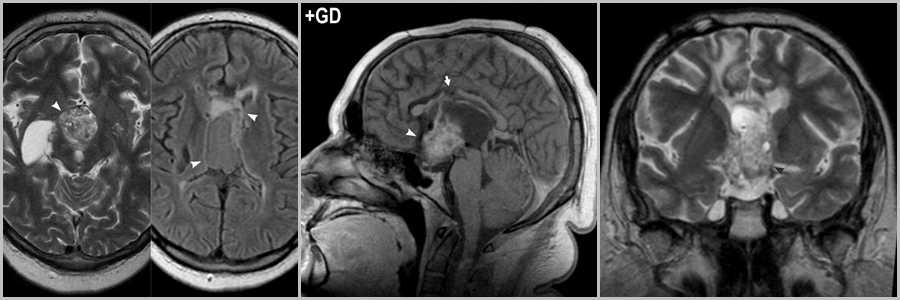

Признаки увеличения степени анаплазии

Появление перифокального отека, увеличение размеров, проявление масс-эффекта характеризует увеличение степени злокачественности опухоли и перерождение ее в анапластическую астроцитому. С увеличением злокачественности опухоль увеличивает клеточность своей стромы, что приводит к ограничению диффузии, отражающемуся на DWI и картах ADC.

При первом исследовании выявляется участок диффузного поражения в височно-затылочной области справа (головки стрелок на рис.187), а так же ограничение диффузии в области поражения (стрелка на рис.188). Кровоизлияний в строме опухоли нет (рис.189).

На исследовании, выполненном через 2,5 месяца определяется увеличение объёма опухоли (головки стрелок рис.190), усиление интенсивности МР-сигнала на DWI (головки стрелок на рис.191), участки кровяного пропитывания (стрелка рис.192), появление участков контрастирования и усиление уже имевшихся (головки стрелок на рис.192).